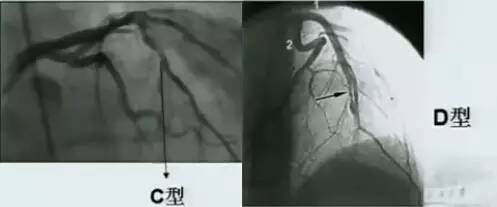

C型:血管壁外造影剂滞留。

D型:螺旋夹层。

图7 动脉夹层C型(左)和D型(右)